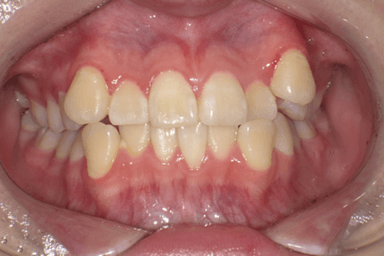

●3か月後

左上の空隙がほぼ閉鎖し、上下顎の正中が合ってきている。(写真b)

b:3か月後